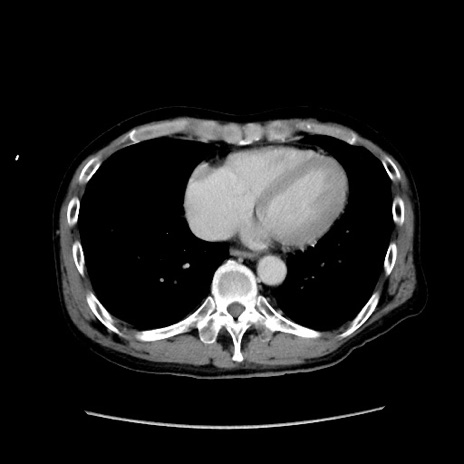

症例

冠状断像